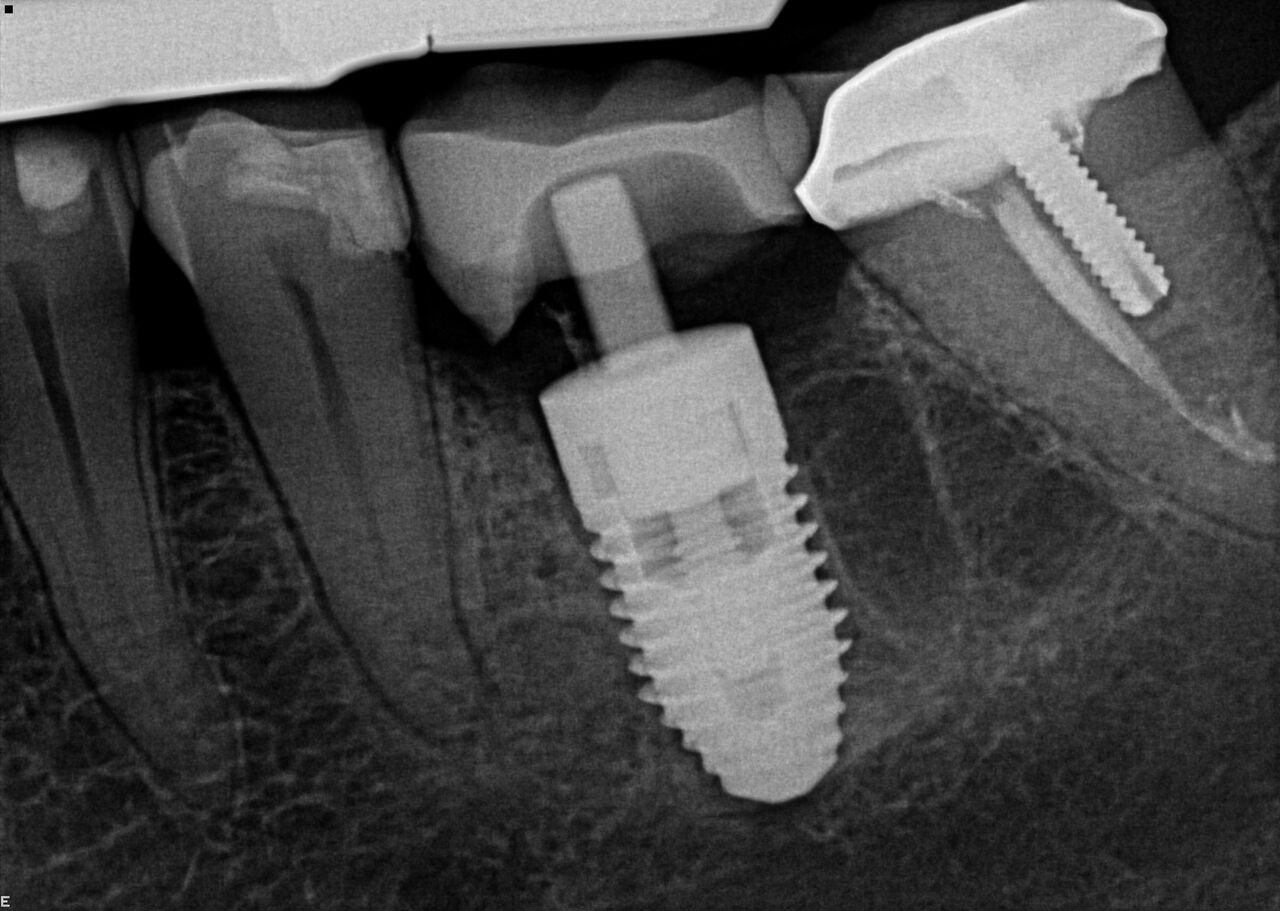

(2.) Immediate implant of No. 19 with temporization abutment.

Figure 2

(4.) Radiograph showing immediate implant of No. 19 with immediate restoration day of surgery.

Figure 4

A 63-year-old woman presented with severe pain on biting of tooth No. 19 (Figure 1). Clinically there was pain on percussion and significant periodontal probing along the mesial root. The patient was anesthetized with infiltration anesthesia and the crown was horizontally sectioned from the lingual of the tooth. The remaining tooth was sectioned so the roots could be extracted individually. The socket was fully debrided and an implant was placed (Figure 2), which was prosthetically correct and stabilized in excess of 45 Ncm. The bone was milled to allow for unimpeded placement of a temporization abutment. The initial crown was revised to be the temporary crown in infraocclusion. Cement was extruded extraorally (Figure 3) prior to seating of the temporary restoration. The socket was sealed with the temporary crown and there were no sutures or bone graft (Figure 4 and Figure 5).